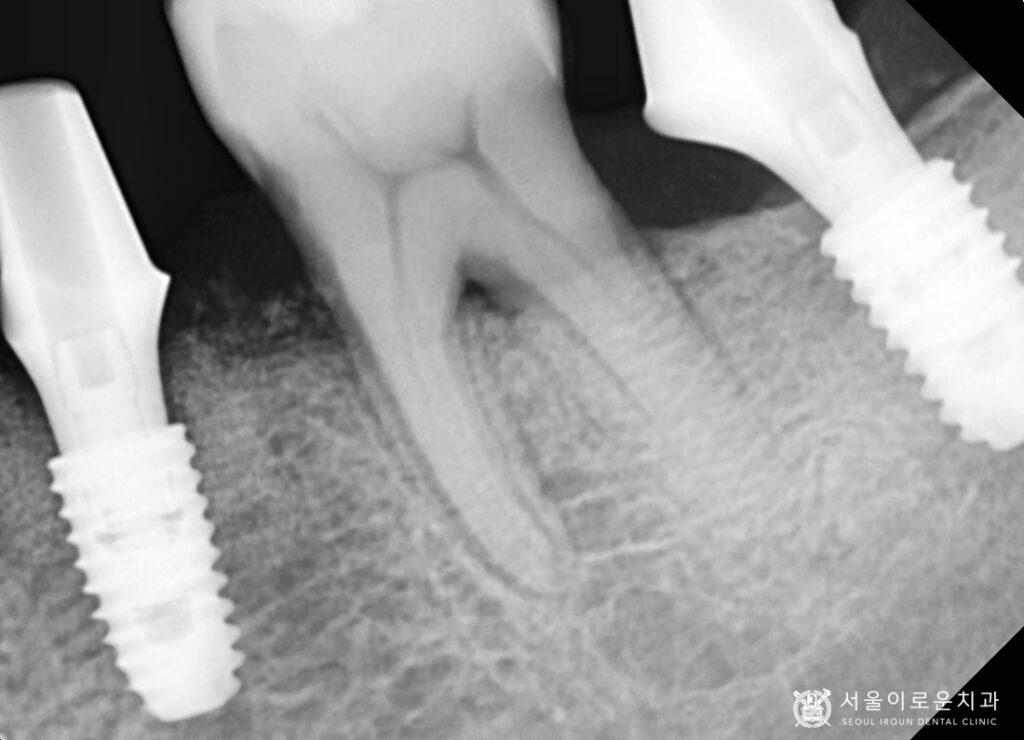

4개의 치아를 발치한 뒤,

뼈이식을 동반한 임플란트를 바로 식립하여

촬영한 x-ray 사진입니다.

기존에 상실되어 없었던

왼쪽 아래 큰 어금니 부위에도

임플란트를 추가로 식립하였습니다. ^^

환.자분의 경우 치주염이 많이 진행된

상태로 잇몸뼈가 상당수 흡수되어

골이식을 동반하였는데요.